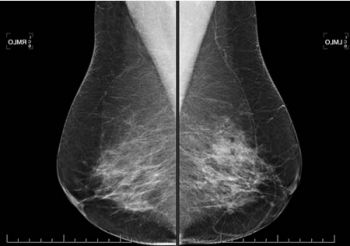

Qu'est qu'une Mammographie ?

Largement utilisé dans le cadre du dépistage du cancer du sein, la mammographie reste l'examen de prédilection pour l'étude de la glande mammaire.

L'appareil fonctionne comme une table de radiographie, mais les rayons utilisés sont de faible énergie afin de s'adapter à la faible densité du tissu mammaire.

Le sein, une fois placé sur le système de détection va être légèrement comprimé afin de répartir l'ensemble des tissus.

En fonction du contexte et des nécessités, plusieurs incidences pourront être réalisées sur chaque sein.